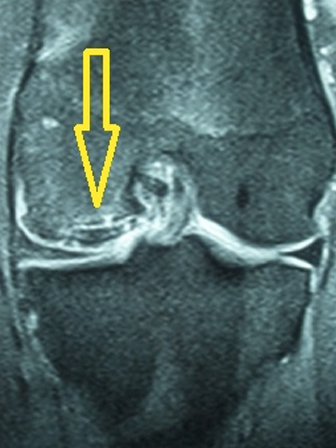

18 yaşında erkek hasta, profesyonel basketbol oyuncusu.

Uzun süredir devam eden diz ağrıları, maç sırasında gelişen burkulma ile artmış. Dizde şişme, ağrı ve basamama şikayetleri ile başvurdu. MR tetkikinde eklem hattında kıkırdak ve kemik içeren büyük bir eklem faresinin serbestleştiği görüldü (Gr 3 Osteochondritis Dissecans)

Hastanın ayrışmakta olan kıkırdak hattı kendi dizinin diğer alanlarından alınan kemikli kıkırdak tüpleri ile artroskopik olarak tespit edildi. (Mozaikplasty Plug Tespiti) Böylece hem ayrışmakta olan kıkırdak tespit edildi hem de ayrışma bölgesi taze kemik ve sitokinlerle tekrar kaynamaya zorlandı.